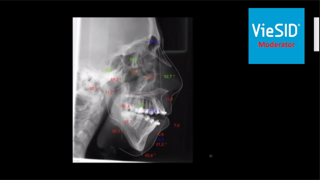

ブラジルの先生も話されていましたが、重要なのは診査・診断です。

術前の診査で、レントゲン写真から導きだされた骨格の角度分析が大変重要になります。